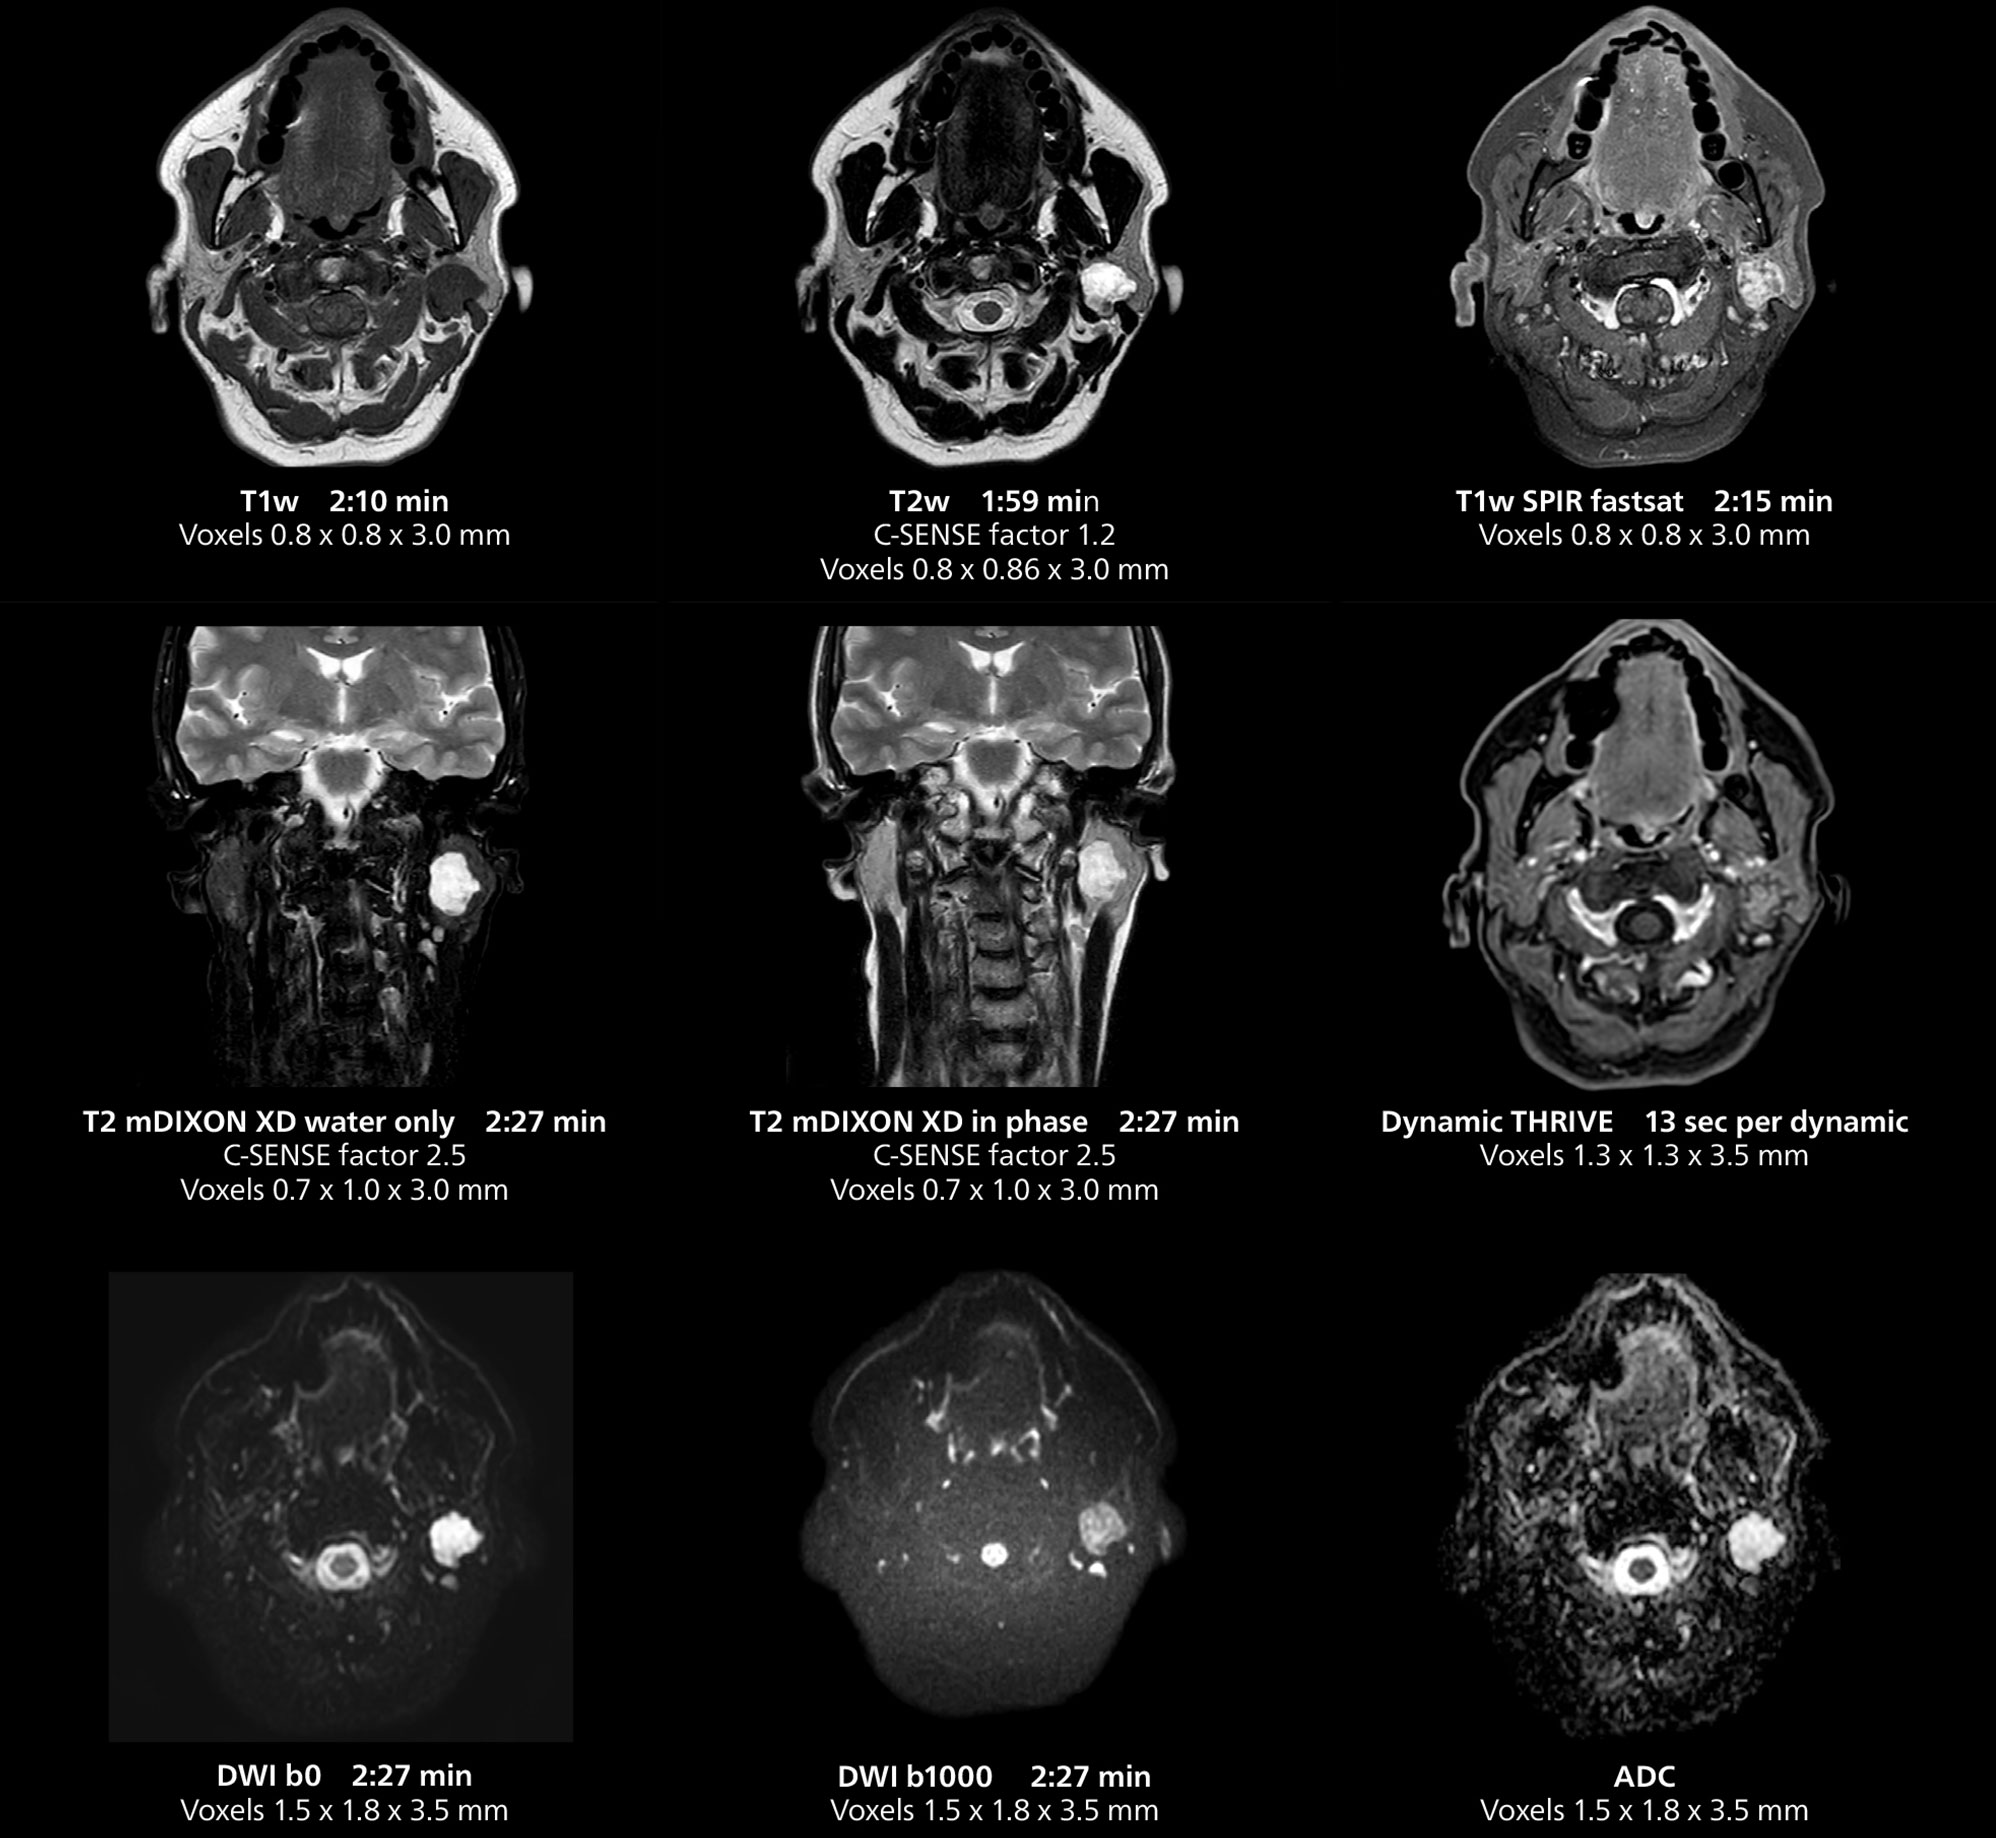

This MRI case illustrates imaging of salivary gland abnormalities with different sequences. Compressed SENSE allows to accelerate scanning while maintaining high quality. With mDIXON XD, different contrast types can be obtained from scanning one sequence.

“We have more speed in 3D sequences,” Dr. Gellée states. “With Compressed SENSE, we can replace two or three 2D scans withone high-quality 3D scan. High quality additional orientations are then obtained by post-processing of the 3D data set, thus saving scanning time.”

Dr. Gellée often takes advantage of the system’s speed to add more sequences to an exam. “When Compressed SENSE reduces typical exam duration, I can add sequences to increase my confidence in diagnosing. For example, post-gadolinium liver scans used to be axial, but now we can use a faster coronal scan. And because I know that the quality will be good the first time, I know I won’t have to repeat the sequence. That frees up time to comfortably add one more sequence,” she says.